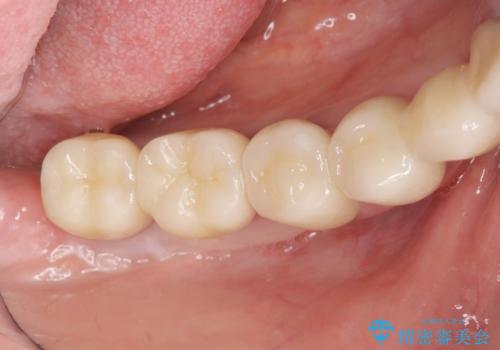

セラミック・インプラント治療を含む包括歯周病治療

- 「銀歯だらけの歯を変えたい。他院で歯周病と指摘されたがクリーニング以外何もしてくれない。」、とセラミック治療歯周病治療を希望され来院されました。

検査の結果、感染根管や欠損、歯周病により残すことのできない歯、等多々問題が認められます。

残すことのできる歯できない歯を選別し、欠損部にはインプラントによる咬合機能の回復、保存できる歯には歯周病治療・根管治療を行う治療計画としました。

銀歯がセラミッククラウンとなり見た目は美しくなりましたが、審美性だけでなく清掃性も向上し、歯ぐきの状態も良好で、歯周病の再発なく経過しています。